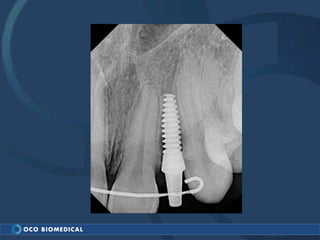

A 3.0mm dental implant was placed to replace congenitally missing maxillary lateral incisors. Dr. Tim Kosinski used a 1.8mm pilot bur and tissue punch to prepare the osteotomy site, then placed the implant by hand and seated it with a torque wrench. After ensuring the implant trajectory was within the restorative envelope, an acrylic coping was placed for temporary fabrication. At the 1 week post-op appointment, excellent soft tissue response and papilla formation were observed, and a final impression was taken to send to the lab for crown fabrication.